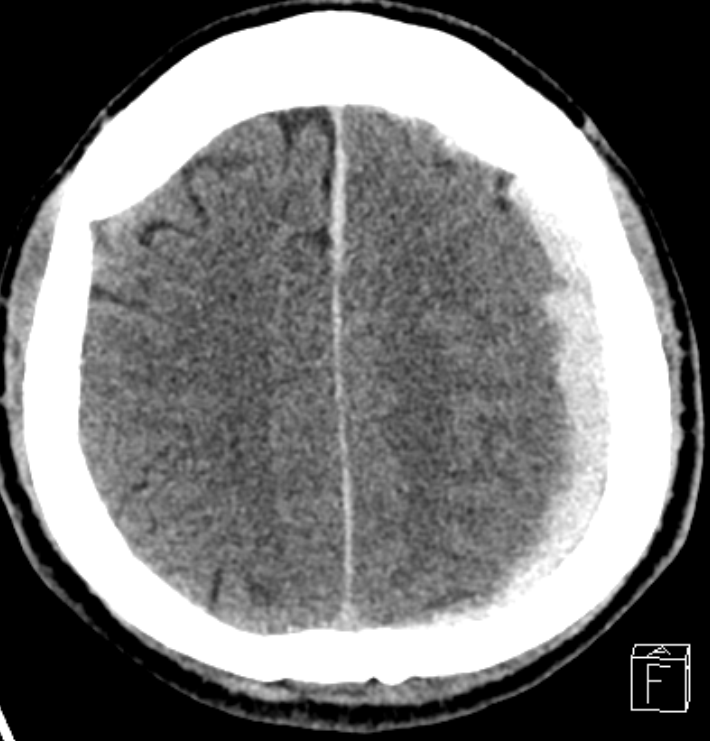

4.파열된 정맥에서 혈액이 경막하강에 고여 CT 상 반월상 형태로 나타남.

6.혈종이 지속적으로 증가하면 뇌 구조물이 반대편으로 밀리는 Midline shifting이 발생하며, 이는 중증 신경학적 손상의 지표로 간주함.